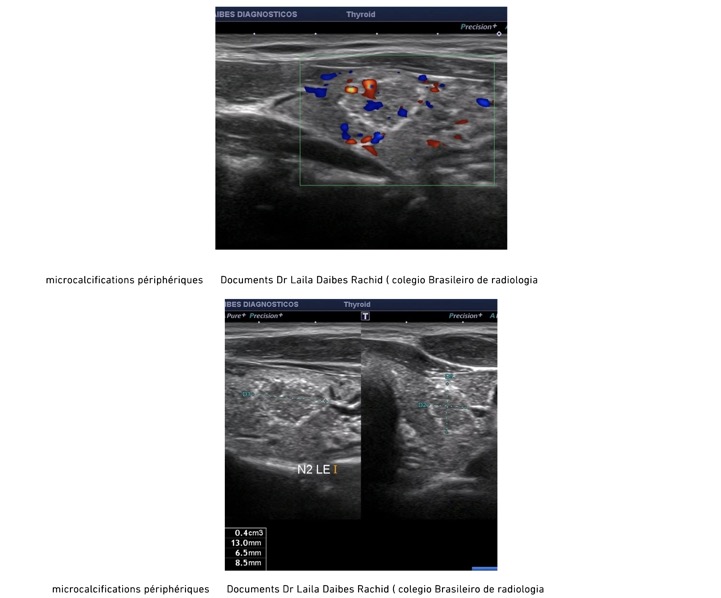

Se méfier des formations hypoéchogènes